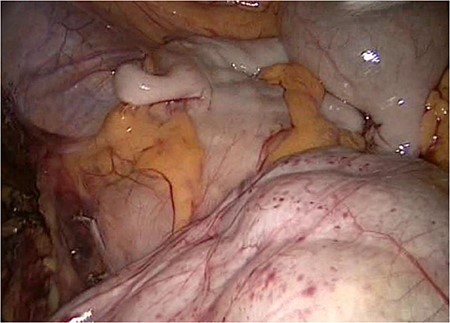

The slim intraperitoneal appendix in the left upper corner with the covered terminal ileum. In the right lower corner, the covered ileum convulse is seen.

We accidentally opened the dorsal peritoneum (Fig. 2), and found the small bowel underneath - retroperitoneal (Fig. 3).

Even the terminal ileum seemed to be retroperitoneal. The slim preperitoneal appendix and the terminal retroperitoneal ileum are demonstrated in Fig. 4. The entire ileum was covered by the peritoneum.